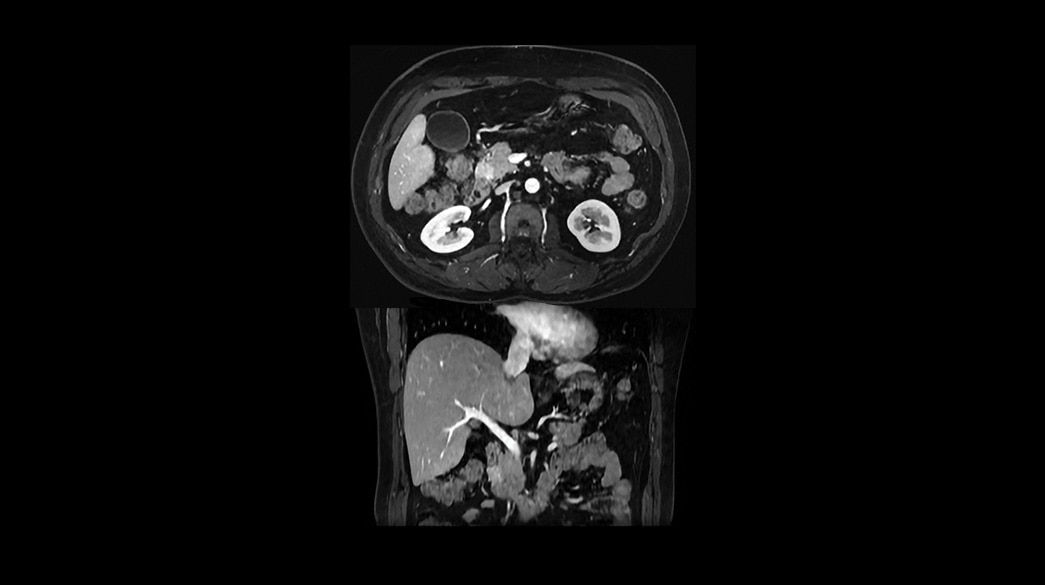

Quantifiable

Provides quantitative and actionable information

Consistent

Motion and distortion-reduced scans with high-resolution and contrast